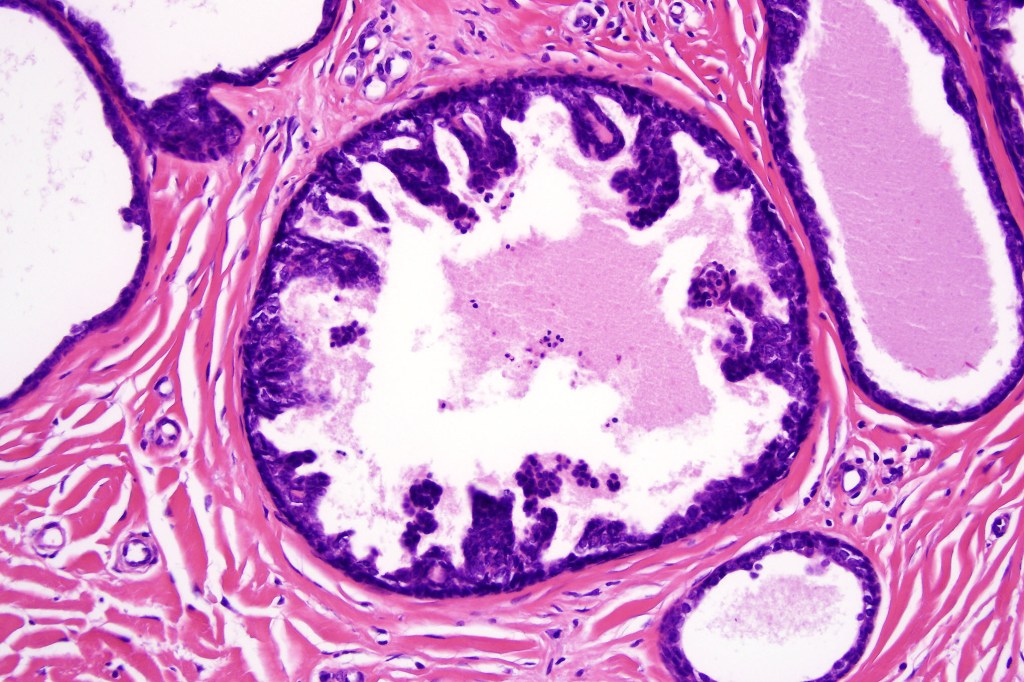

•Ducts lined by double-layered epithelium- small inner, uniform cells with eosinophilic cytoplasm & vesicular/hyperchromatic nuclei with small nucleoli & outer myoepithelial cells

•Pseudo-papillae (devoid of a fibrovascular core) are often conspicuous

Absense of true papillae (i.e with a fibrovascular core)

•Variable cribriform pattern